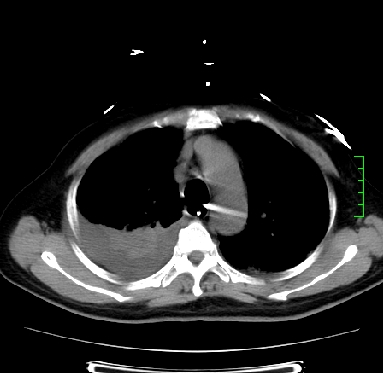

icu病人,几天都没明确诊断。m,76y,咳嗽、咳痰1周,伴气促,右胸痛入院,pe:t38.3c p135 r25 bp135/85。双肺可闻及大量湿罗音,心、腹未见明显异常。诊断:1心衰?2肺部感染?3冠心病?

双肺感染性病变,下叶膨胀不全,胸水,左室大。

1)两肺感染性病变(右肺下叶肺脓肿可能)。2)双侧胸腔积液,以右侧为甚。

混合型肺水肿合并感染,肺膨胀不全,胸膜肥厚粘连包裹,同时肺内有陈旧性病灶。注意复查

ards,肺感染性病变,右下叶实变,双侧胸腔积液,右侧为著,叶间胸膜积液,右上肺陈旧性tb纤维灶,左室大。

考虑双肺感染、右肺下叶肺脓肿伴双侧胸腔积液,肺水肿。

考虑:双肺感染、右肺下叶肺脓肿,双侧胸腔积液,肺水肿.请结合临床.